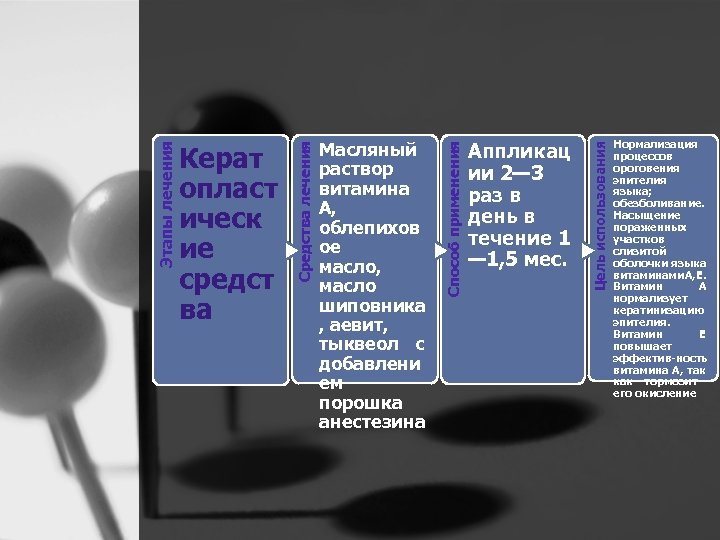

Аппликац ии 2— 3 раз в день в течение 1 — 1, 5 мес. Цель использования Способ применения Средства лечения Этапы лечения Керат опласт ическ ие средст ва Масляный раствор витамина А, облепихов ое масло, масло шиповника , аевит, тыквеол с добавлени ем порошка анестезина Нормализация процессов ороговения эпителия языка; обезболивание. Насыщение пораженных участков слизитой оболочки языка витаминами А, Е. Витамин А нормализует кератинизацию эпителия. Витамин Е повышает эффектив ность витамина А, так как тормозит его окисление